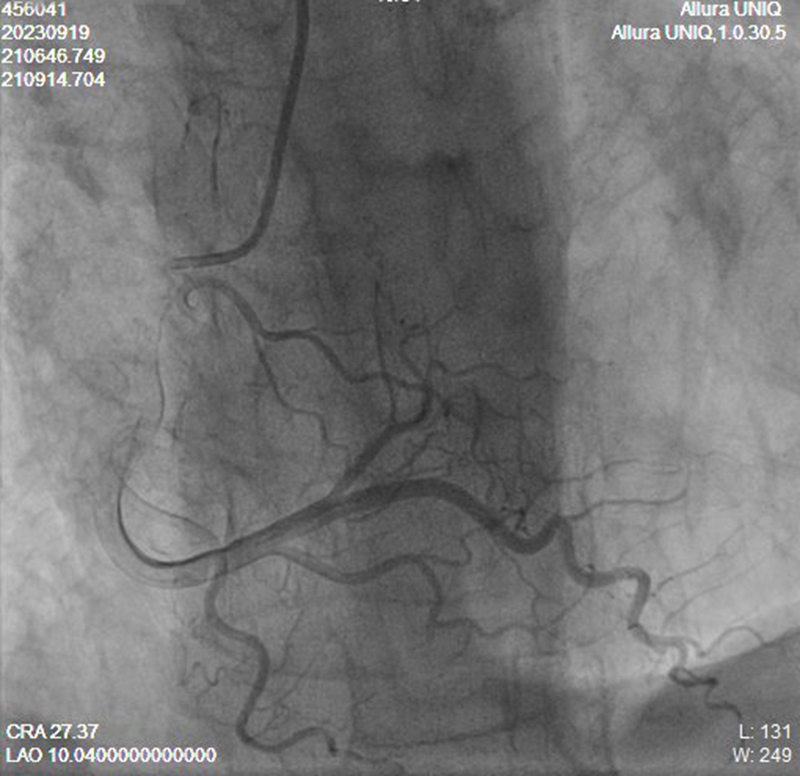

心脏供血的血管主要包括冠状动脉左主干,以及右冠状动脉。其中左主干血管为心脏提供三分之二以上的血液供应,左主干闭塞引起的急性心肌梗死,是危险程度最高、存活率最低的一种类型,不少患者猝死于院外,即使有机会到达医院接受急诊介入手术,死亡率仍高达50%以上。

【右冠状动脉造影,显示无侧支循环生成来保护左主干供血区域】